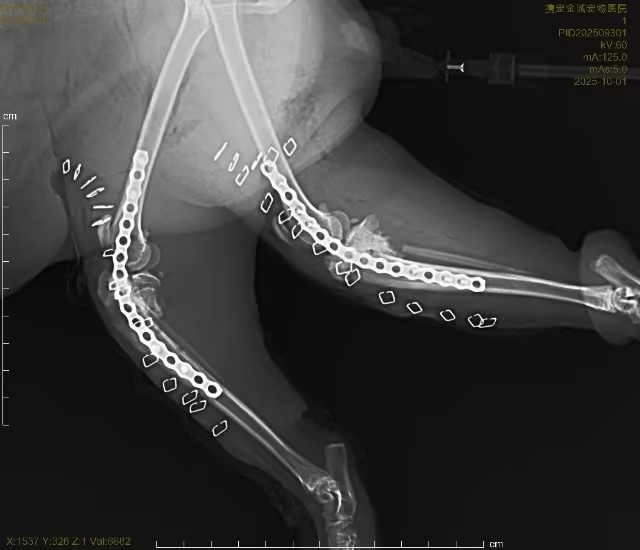

四、核心诊疗亮点:联合浙江大学教授·骨02胶水微创骨骼修复手术

针对猫咪高空坠落导致的骨骼创伤,我院启动重症创伤多学科联合救治,突破传统手术局限:

- 专家联合主刀:特邀浙江大学权威骨科教授亲临我院,全程指导并参与手术,保障手术安全性与精准度

- 创新技术应用:采用骨02胶水进行骨骼微创固定手术并结合传统钢板、钢钉固定

手术优势:

- 创口极小,对坠楼后虚弱机体损伤更低

- 骨骼固定牢固,稳定性强

- 术后愈合快,大幅缩短康复周期

- 减少感染、出血、二次损伤等并发症

- 联合救治:手术同期开展保肝、护肾、纠正凝血、控制炎症、纠正代谢紊乱等综合重症支持治疗,实现“骨骼修复+内脏保护”双保障。